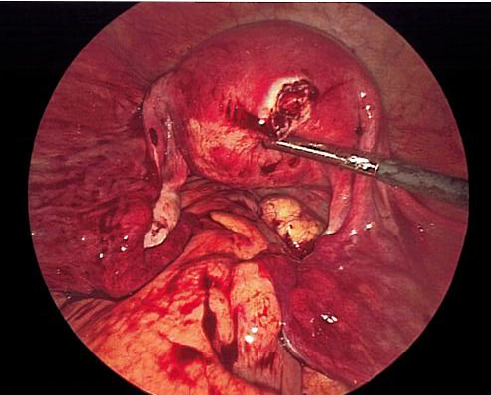

On exam, her vital signs were within normal limits. Abdominal exam revealed significant tenderness to palpation throughout the lower abdomen along with rebound tenderness. Laboratory evaluation revealed a hemoglobin of 11.9 g/dL and β human chorionic gonadotropin of 1,686 mIU/mL. Transabdominal and transvaginal ultrasound revealed a normal appearing uterus measuring 9.6 x 5.0 x 5.5 cm with no identified intrauterine gestational sac or yolk sac. There was noted to be a non-specific heterogenous, nonvascular mass of the right adnexa with no pelvic free fluid noted (Figure 1).